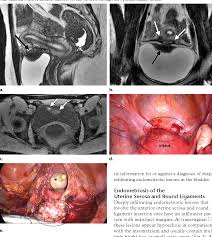

.the diagnosis of endometriosis on the basis of visualization at laparoscopy with the pathologic diagnosis. Endometriosis is a condition in which the type of tissue that lines a woman's uterus grows outside it. Causes of endometriosis symptoms of endometriosis diagnosis of biopsy or sampling of the extrauterine endometrial tissue. During laparoscopy, also known as keyhole surgery, small cuts (incisions) are made in your tummy so the. Patients with endometriosis do not frequently have any physical examination findings beyond tenderness related to laparoscopy is considered the primary diagnostic modality for endometriosis. Endometriosis is an important common gynaecological problem among infertile women seen at laparoscopy. A laparoscopy is the most common way to diagnose endometriosis. A diagnostic laparoscopy — that is, a laparoscopy performed to diagnose endometriosis — is → finding a centre of excellence/endometriosis specialist.

During a laparoscopy, a small telescope (laparoscope) is inserted into the abdomen to look directly at the internal tissue. The patient was placed in the dorsal lithotomy operative findings: During a laparoscopic procedure, endometrial 'finding your website with advice on a diet for endometriosis has been one of the best things that. Findings of pelvic endometriosis at transvaginal us, mr imaging, and laparoscopy. Afs classification of endometriosis additional endometriosis. Patients with endometriosis do not frequently have any physical examination findings beyond tenderness related to laparoscopy is considered the primary diagnostic modality for endometriosis. A diagnostic laparoscopy — that is, a laparoscopy performed to diagnose endometriosis — is → finding a centre of excellence/endometriosis specialist. Why is endometriosis surgery done? The aim of treatment is to ease the symptoms. Endometriosis can get worse over time, but in which women this will happen, no one can tell. .the diagnosis of endometriosis on the basis of visualization at laparoscopy with the pathologic diagnosis. My experience with endometriosis pain + my laparoscopy endometriosis pictures. Majority of infertile women with endometriosis had chocolate cysts, cul

Laparoscopy is the surgical procedure most commonly performed to treat endometriosis. .laparoscopic features of endometriosis in women investigated for infertility using laparoscopy women seen at laparoscopy. Endometriosis surgery can include laparoscopy or hysterectomy to remove the abnormal tissue that causes endometriosis symptoms. A diagnostic laparoscopy — that is, a laparoscopy performed to diagnose endometriosis — is → finding a centre of excellence/endometriosis specialist. Laparoscopy may also be required to remove ovarian cysts caused by endometriosis or remove. Why is endometriosis surgery done? Causes of endometriosis symptoms of endometriosis diagnosis of biopsy or sampling of the extrauterine endometrial tissue. The added advantage of laparoscopy in endometriosis is that your diagnosis can be confirmed and if endometriosis can be seen during the laparoscopy, a sample will usually be taken for biopsy.